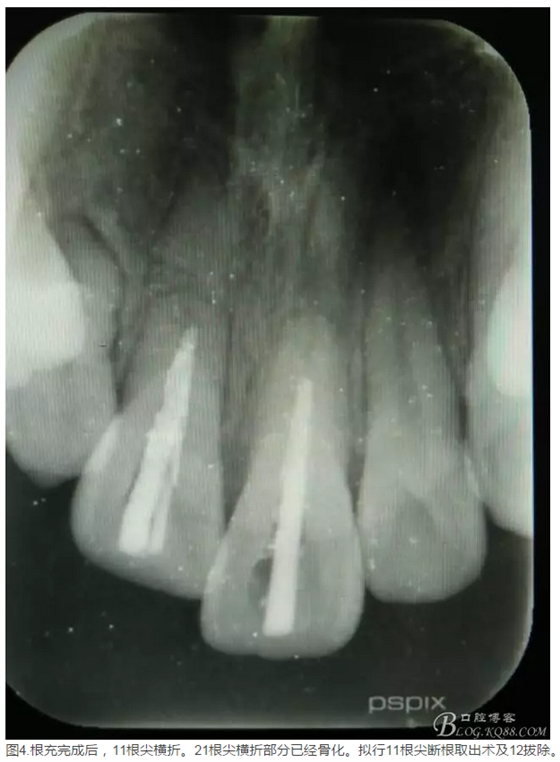

患者、李xx、男、15歲,主訴:牙不齊,矯正牙齒。??茩z查:發(fā)現(xiàn)11、21根尖三分之一折斷,患者否認(rèn)有外傷史。正畸科治療建議如圖1.。術(shù)前簽手術(shù)同意書。